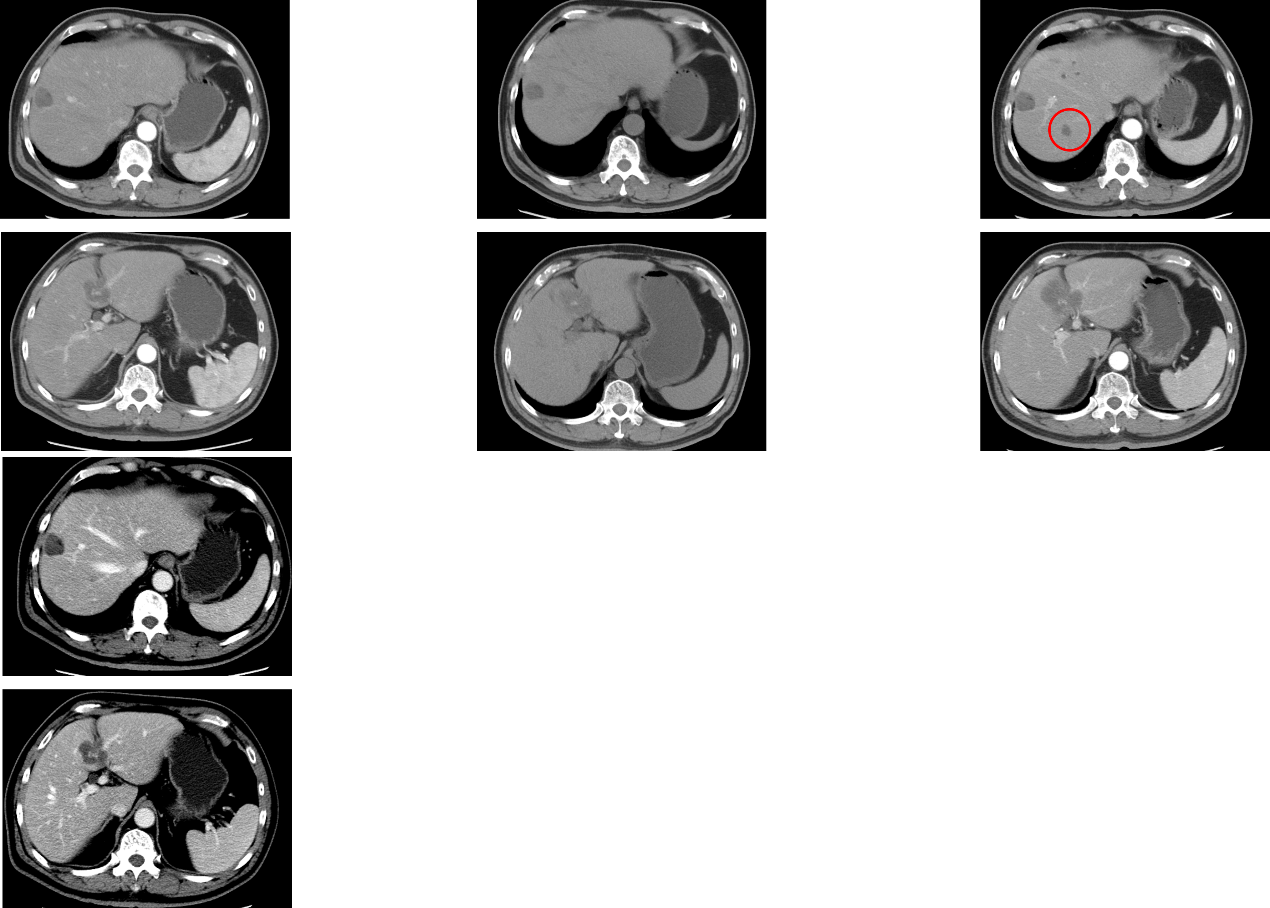

2018-06-06 全身治疗前胸腹盆增强CT基线检查:肝内多发低密度灶,转移瘤射频治疗后改变;直肠癌术后改变。

图1. 基线(2018-06-06)胸腹盆增强CT